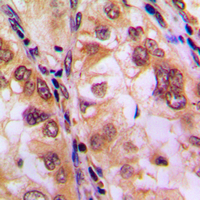

IHC (Immunohiostchemistry)

(Immunohistochemical analysis of Histone Deacetylase 8 (pS39) staining in human lung cancer formalin fixed paraffin embedded tissue section. The section was pre-treated using heat mediated antigen retrieval with sodium citrate buffer (pH 6.0). The section was then incubated with the antibody at room temperature and detected using an HRP conjugated compact polymer system. DAB was used as the chromogen. The section was then counterstained with haematoxylin and mounted with DPX.)